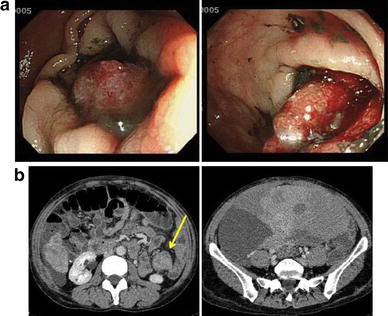

Colonoscopy and CT images 2 months after onset. a Captured images during colonoscopy. Compared with Fig. 1c, the tumor had grown so rapidly that the lumen was subtotally occluded. b CT images of the colon and pelvic tumors. Left panel Upper colon from the stenosis site at the sigmoid with a massive tumor is enlarged. Arrow indicates the lesion. Right panel Pelvic tumor is also extremely increased in size compared with that in the former images

Dr. Takase: The upper colon from the stenosis site at the sigmoid with massive tumor was enlarged. Compared with that in the CT images obtained at the former hospital, the ovarian tumor was also extremely enlarged (Fig. 4b).